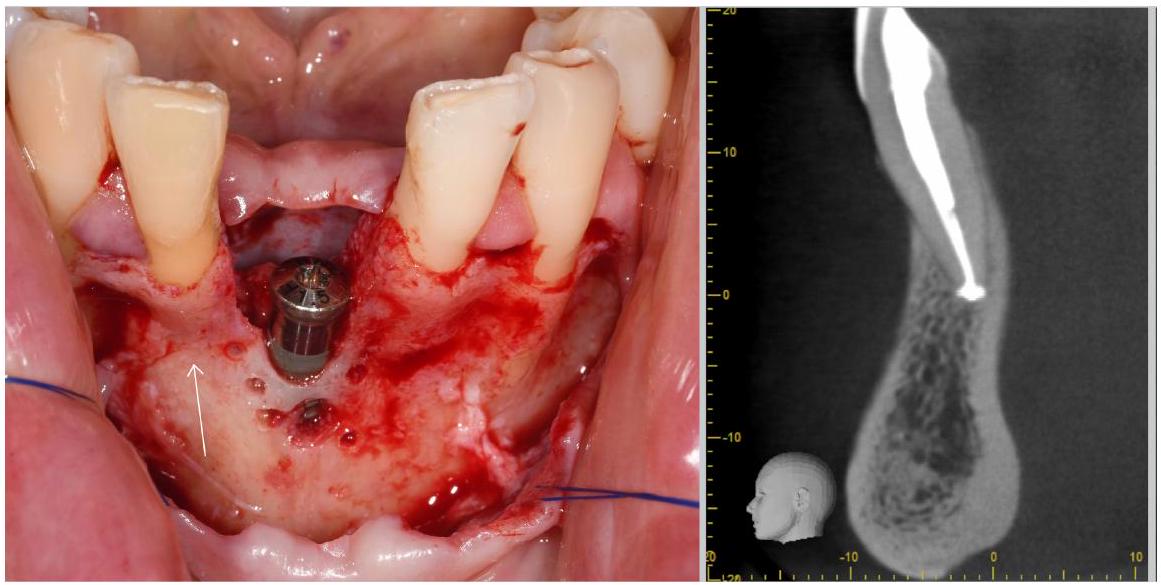

- أثناء المسح، يجب فصل الأنسجة الرخوة الوجهية (الشفاه) عن قمة الحويصلات، على سبيل المثال، بواسطة لفة قطنية موضوعة في الفم لزيادة التباين المحلي.

- During the scan, facial soft tissue (lip) should be separated from the alveolar crest, for example, by a cotton roll placed in the vestibulum to increase local contrast.

or the supracrestal tissue dimensions, the combination of a CBCT with an optical surface scan can provide more accurate results.